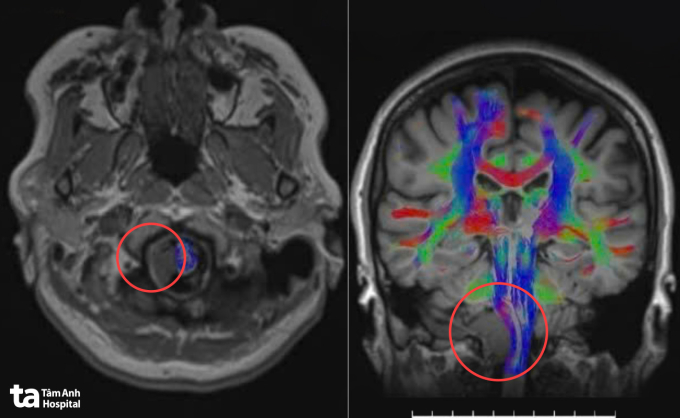

Ảnh MRI 3 Tesla cho thấy khối u nằm sâu vùng góc hành não của bà Hạnh. Ảnh: Bệnh viện Đa khoa Tâm Anh

Trước khi mổ, robot AI sử dụng công nghệ hòa hình đa lớp, tích hợp dữ liệu từ MRI và CT để tái tạo mô hình não 3D với độ phân giải cao. Nhờ đó, êkíp xác định rõ vị trí, kích thước cũng như mối liên quan giữa khối u và các dây thần kinh sọ 9, 10, 11, 12 cùng mạch máu nền sọ, lập kế hoạch tiếp cận tối ưu qua cửa sổ C1 – vùng nối giữa cổ và nền sọ.